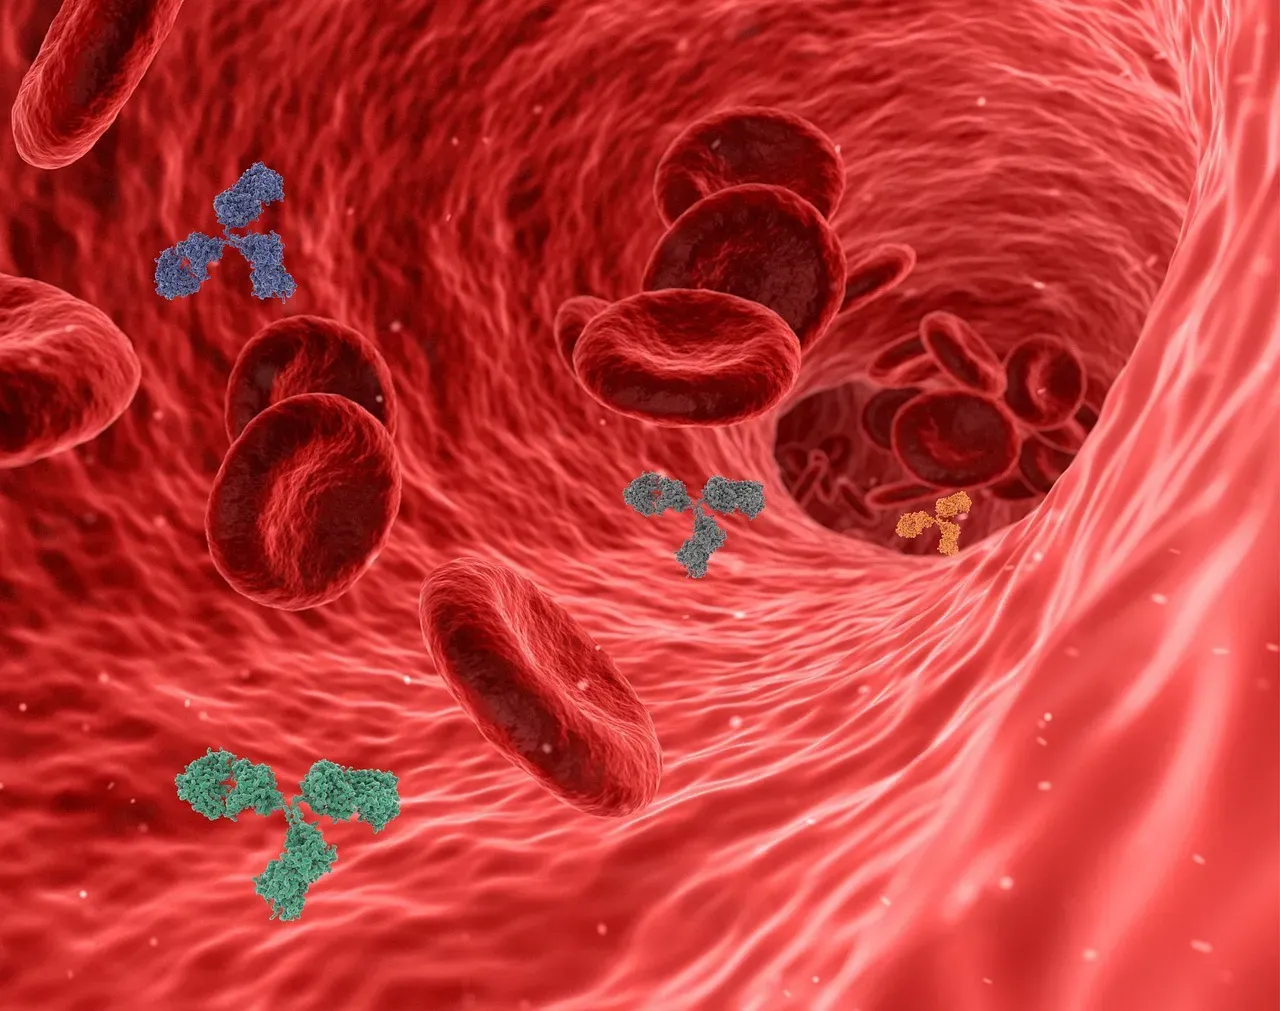

Every day, your immune system is waging countless tiny battles you never feel or see. Bacteria on your skin, viruses in the air, and abnormal cells that pop up from everyday DNA copying errors all get scanned, tagged, and, if needed, destroyed. White blood cells patrol like neighborhood guards, antibodies recognize familiar threats from past infections or vaccines, and inflammation acts as an alarm system calling in reinforcements. When everything works smoothly, you stay healthy and barely notice that anything happened at all.

What’s truly fascinating is that your immune system learns from experience and can refine its response over time. Vaccines essentially train it like a rehearsal before a real performance, so when the actual pathogen appears, your body already knows the moves. On the flip side, when the system gets confused, it can overreact to harmless things like pollen, or even attack your own tissues in autoimmune diseases. That’s where lifestyle choices like sleep, stress management, and diverse nutrition come in, because they support a more balanced immune response. It’s not about “boosting” everything blindly; it’s about helping your internal defense team distinguish friend from foe more accurately.